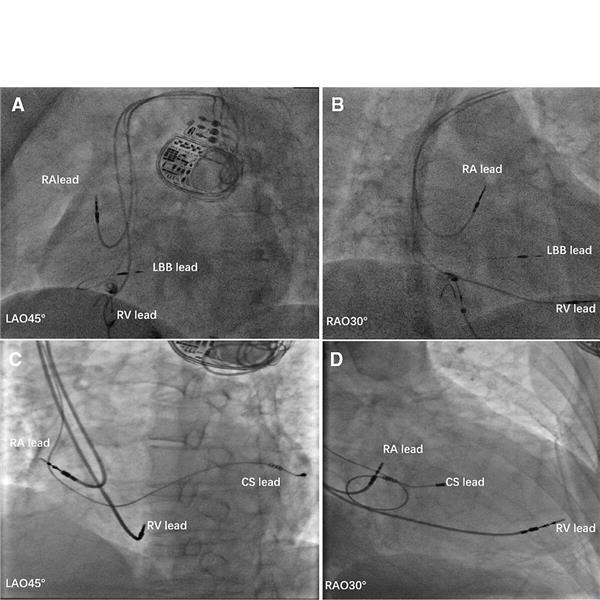

Repräsentative Bilder der Sonden von LBBAP und BiVP, siehe unten.

![Leitungssystem spezifisch stimulieren Repräsentative Bilder der Sonden von LBBAP (A, B) und BiVP (C, D). Juan Hua [5]](/Bilder/Repraesentative-Bilder-der-Sonden-von-LBBAP-A-B-und-BiVP-C-218330.jpg)

Repräsentative Bilder der Sonden von LBBAP (A, B) und BiVP (C, D). Juan Hua [5]